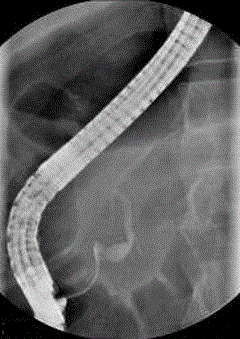

Figure 2. Endoscopic retrograde pancreatogram showing focal cystic dilation of the terminal part of the main pancreatic duct